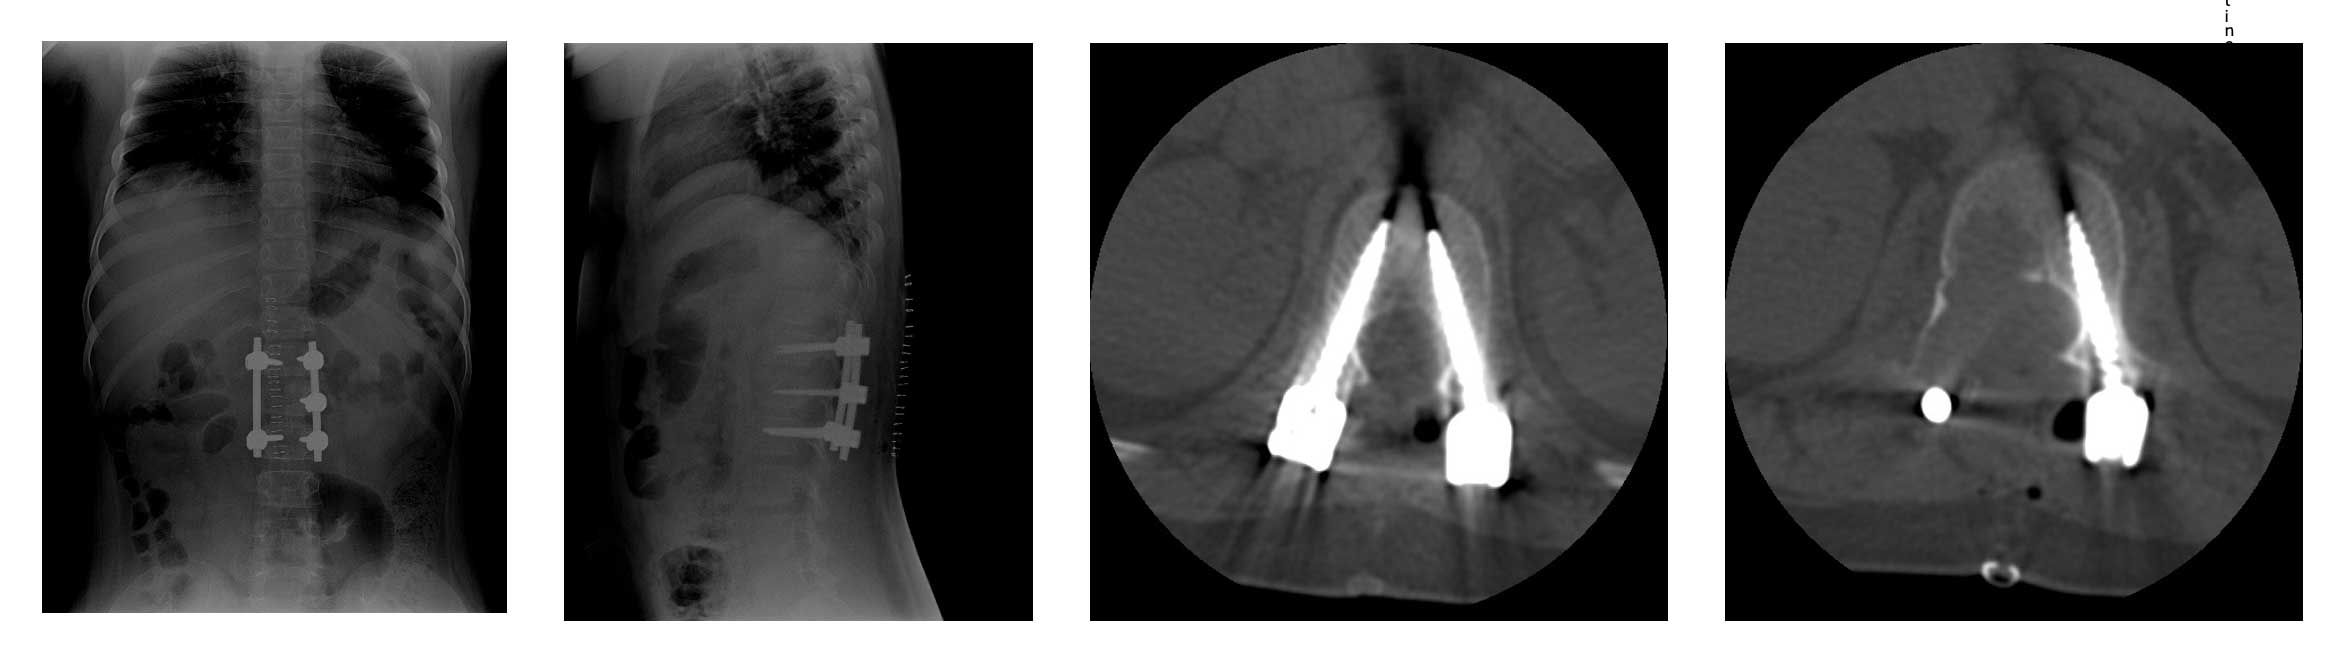

Ameliyat Öncesi: Tomografide birinci lomber omurga sağ taraf yerleşimli osteoid osteoma için tipik nidus görülmekte.

Ameliyat Sonrası: Röntgende ve tomografide tümör temizlendikten sonra vidalama işleminin mümtazam uygulaması görülmekte.